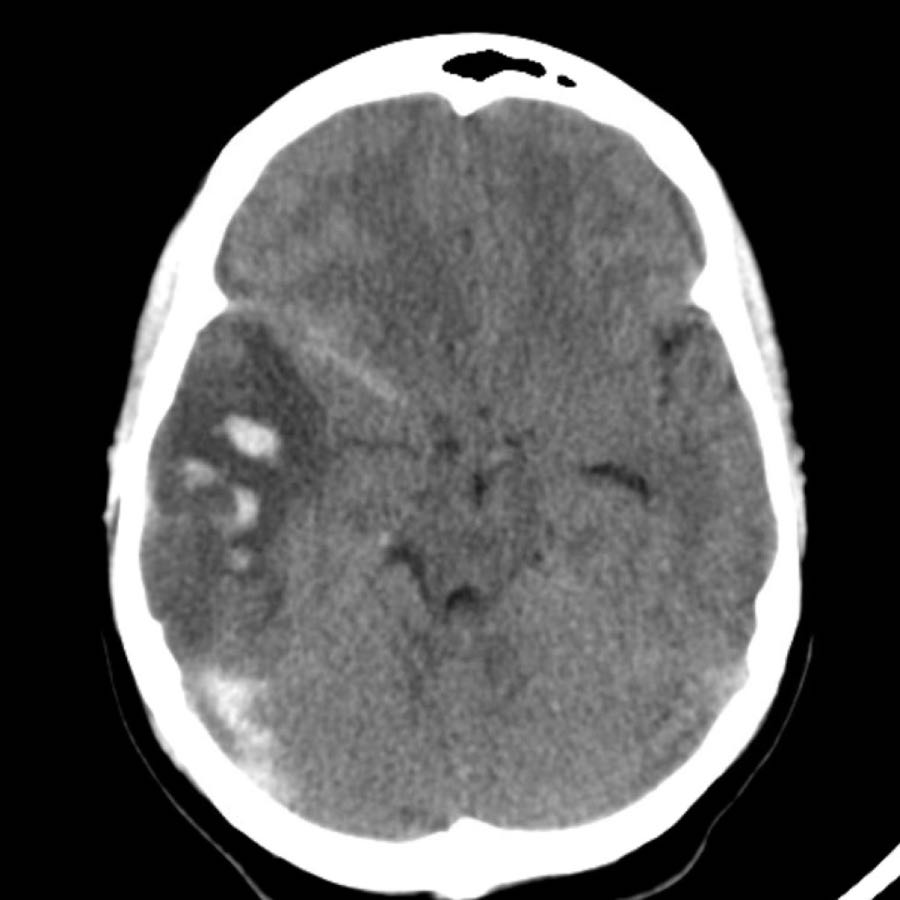

Các hình ảnh CT cho thấy:

- Xuất huyết thùy não trên phim CT không tiêm thuốc cản quang (NECT).

Ngoài ra còn có một ít máu dưới nhện.